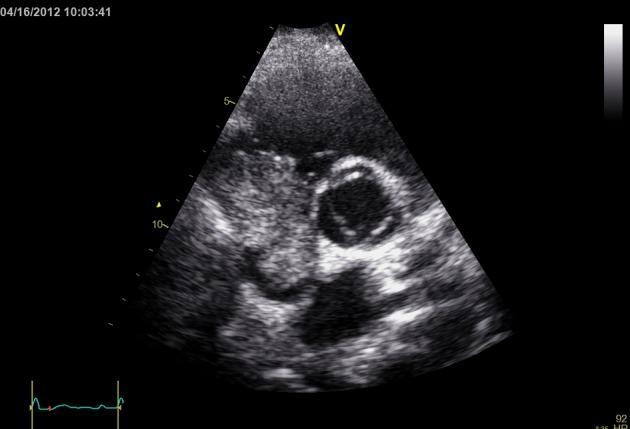

A 41-year-old man presented to the emergency room for evaluation of substernal chest pain, shortness of breath and generalized failure to thrive. Patient had history of hepatitis B and HIV. During recent evaluation of hepatic mass, patient was found to have hepatocellular carcinoma on biopsy. Patient had no history of cirrhosis of the liver in the past. On Echocardiogram patient was noted to have a large mass filling the right atrial cavity. CT scan of abdomen, pelvis and chest showed a diffusely enlarged heterogeneously enhancing liver consistent with large hepatoma, with portal venous and hepatic vein thrombosis. Tumor thrombus extended through the hepatic veins and upper inferior vena cava into the right atrium. There was 6 cm greatest diameter enhancing mass in the right atrium. Patient had primary hepatocellular carcinoma with extensive invasion into vascular structures. His prognosis was poor and patient opted for palliative care only. In conclusion, patients with co-infection of HIV and Hepatitis B are at risk of developing hepatocellular carcinoma with extension into the right atrium and physicians managing these patients should have high suspicion of right atrial involvement with tumor extension and low threshold to order a screening echocardiogram.

一名41岁男性因胸骨后胸痛、呼吸急促和全身发育不良前来急诊室就诊。患者有乙肝和艾滋病毒感染史。近期在评估肝脏肿块时,活检发现患者患有肝细胞癌。患者既往无肝硬化病史。超声心动图显示患者右心房腔内有一个大肿块。腹部、骨盆和胸部的CT扫描显示肝脏弥漫性肿大,强化不均匀,符合大肝癌表现,伴有门静脉和肝静脉血栓形成。肿瘤血栓通过肝静脉和上下腔静脉延伸至右心房。右心房内有一个最大直径为6cm的强化肿块。患者患有原发性肝细胞癌并广泛侵犯血管结构。他的预后很差,患者仅选择了姑息治疗。总之,艾滋病毒和乙肝合并感染的患者有发生肝细胞癌并延伸至右心房的风险,治疗这些患者的医生应高度怀疑肿瘤延伸累及右心房,并应积极进行筛查超声心动图检查。